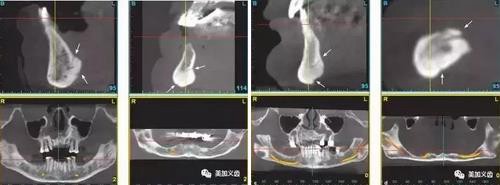

3、下頜中線處不建議種植。

4、無(wú)牙頜患者牙槽骨嚴(yán)重吸收者,舌頦動(dòng)脈離牙槽嵴頂近,種植體植入易傷及舌頦動(dòng)脈。

5、術(shù)前一定要拍CT,研究植入位點(diǎn)解剖結(jié)構(gòu)。